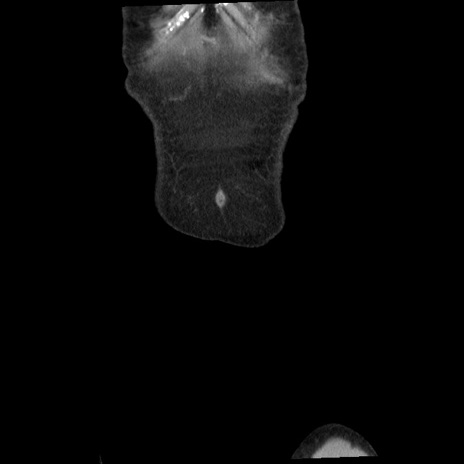

矢状断像